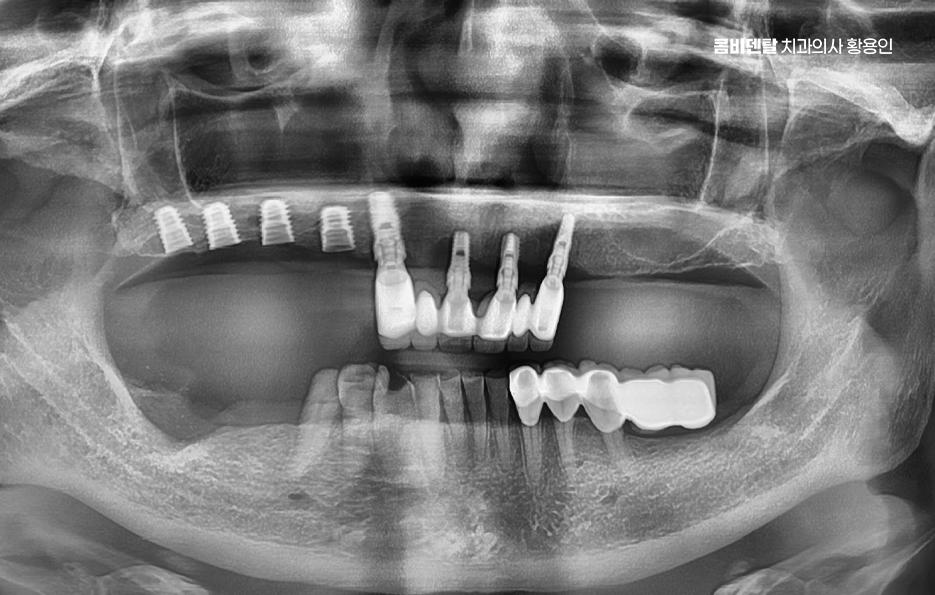

앞니 임플란트가 주로 심미성을 중심으로 고려된다면, 어금니 임플란트는 씹는 기능과 직결되는 치료이기 때문에 하중, 뼈 상태, 장기적인 안정성까지 함께 고려해야 하는데 실제로 음식을 씹을 때 사용되는 힘의 대부분은 어금니에 집중되며 이 어금니가 빠진 상태로 오래 지내거나, 상태를 충분히 고려하지 않고 임플란트를 진행하면 여러 문제가 생길 수 있었어요.

어금니 부위는 씹는 힘이 강한 만큼, 임플란트에 전달되는 하중도 커서 단순히 임플란트를 심는 것뿐 아니라, 그 힘을 어떻게 분산시킬 것인지에 대한 계획이 중요한데 임플란트의 위치, 각도, 크기, 그리고 위에 올라가는 보철물의 형태까지 함께 고려되어야 하며 이 과정이 충분히 고려되지 않으면, 임플란트 자체는 괜찮아 보여도 시간이 지나면서 주변 뼈에 무리가 가거나, 보철물이 깨지는 문제가 생길 수 있어요.

이제 어금니 임플란트 뼈이식이 필요한 케이스에 대해 좀더 알아보면 뼈이식은 임플란트를 심기 위한 뼈가 부족할 때, 뼈의 양이나 형태를 보완하기 위해 시행되는 치료로서 많은 분들이 뼈이식에 대해 부담과 걱정을 느끼시곤 하는데 뼈이식은 임플란트를 더 안전하게 하기 위한 준비 과정이라고 이해하는 것이 좋을 거예요

뼈이식이 필요하다고 해서 모두 같은 방식으로 진행되는 것은 아니며 부족한 뼈의 양과 위치에 따라 치료 방법과 범위는 달라지며 소량의 보완만 필요한 경우에는 임플란트를 심으면서 동시에 진행되기도 하고, 뼈 상태가 많이 부족한 경우에는 일정 기간 뼈가 자리 잡을 시간을 갖고 나서 임플란트를 진행하기도 해서 이 과정은 개인 상태에 따라 달라지기 때문에, 획일적으로 생각하기보다는 맞춤 계획으로 접근해야 하는 거예요

어금니 임플란트는 단순히 빠진 치아를 대신하는 치료가 아니라, 전체 치아 구조와 씹는 균형을 회복하는 치료이기 때문에 치료를 시작하기 전에 지금 이 상태에서 나에게 적절하고 안전한 방법이 무엇인가를 충분히 고민해야 하며 뼈이식이 필요하다는 말은 치료가 더 어려워졌다는 의미가 아니라, 더 안정적인 결과를 위한 준비가 필요하다는 의미에 가까우며 임플란트는 당장의 치료만이 아니라 장기적으로 수명 유지를 안정적으로 해야 하므로 장기적인 관점으로 치료를 계획하시길 바라고 있어요